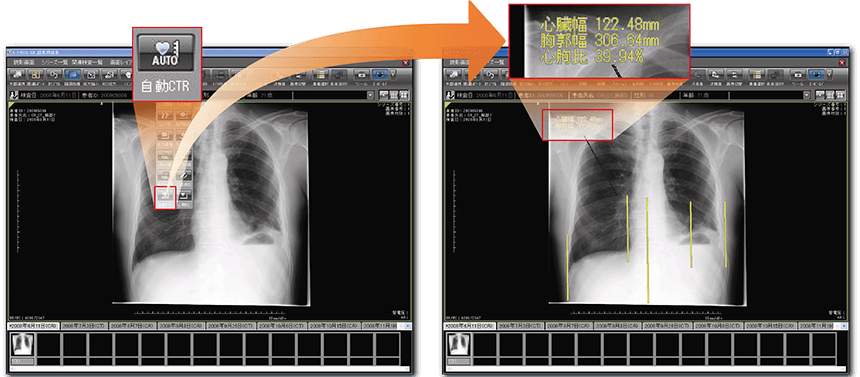

整形計測機能

コブ角計測、FTA、Sharp角、CE角、AHI、脊柱管狭小率、外反母趾角などの各種整形計測機能を搭載。整形領域のフィルムレス化を支援します。 ※オプション